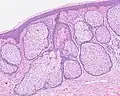

H&E staining of biopsied lesion of sebaceous hyperplasia: Note the multiple, mature sebaceous lobules attached to the central dilated duct in the upper dermis. -

Sebaceous hyperplasia shares histopathological similarities with the typical architecture of the folliculosebaceous unit, but with larger and expanded sebaceous glands.[12][13]